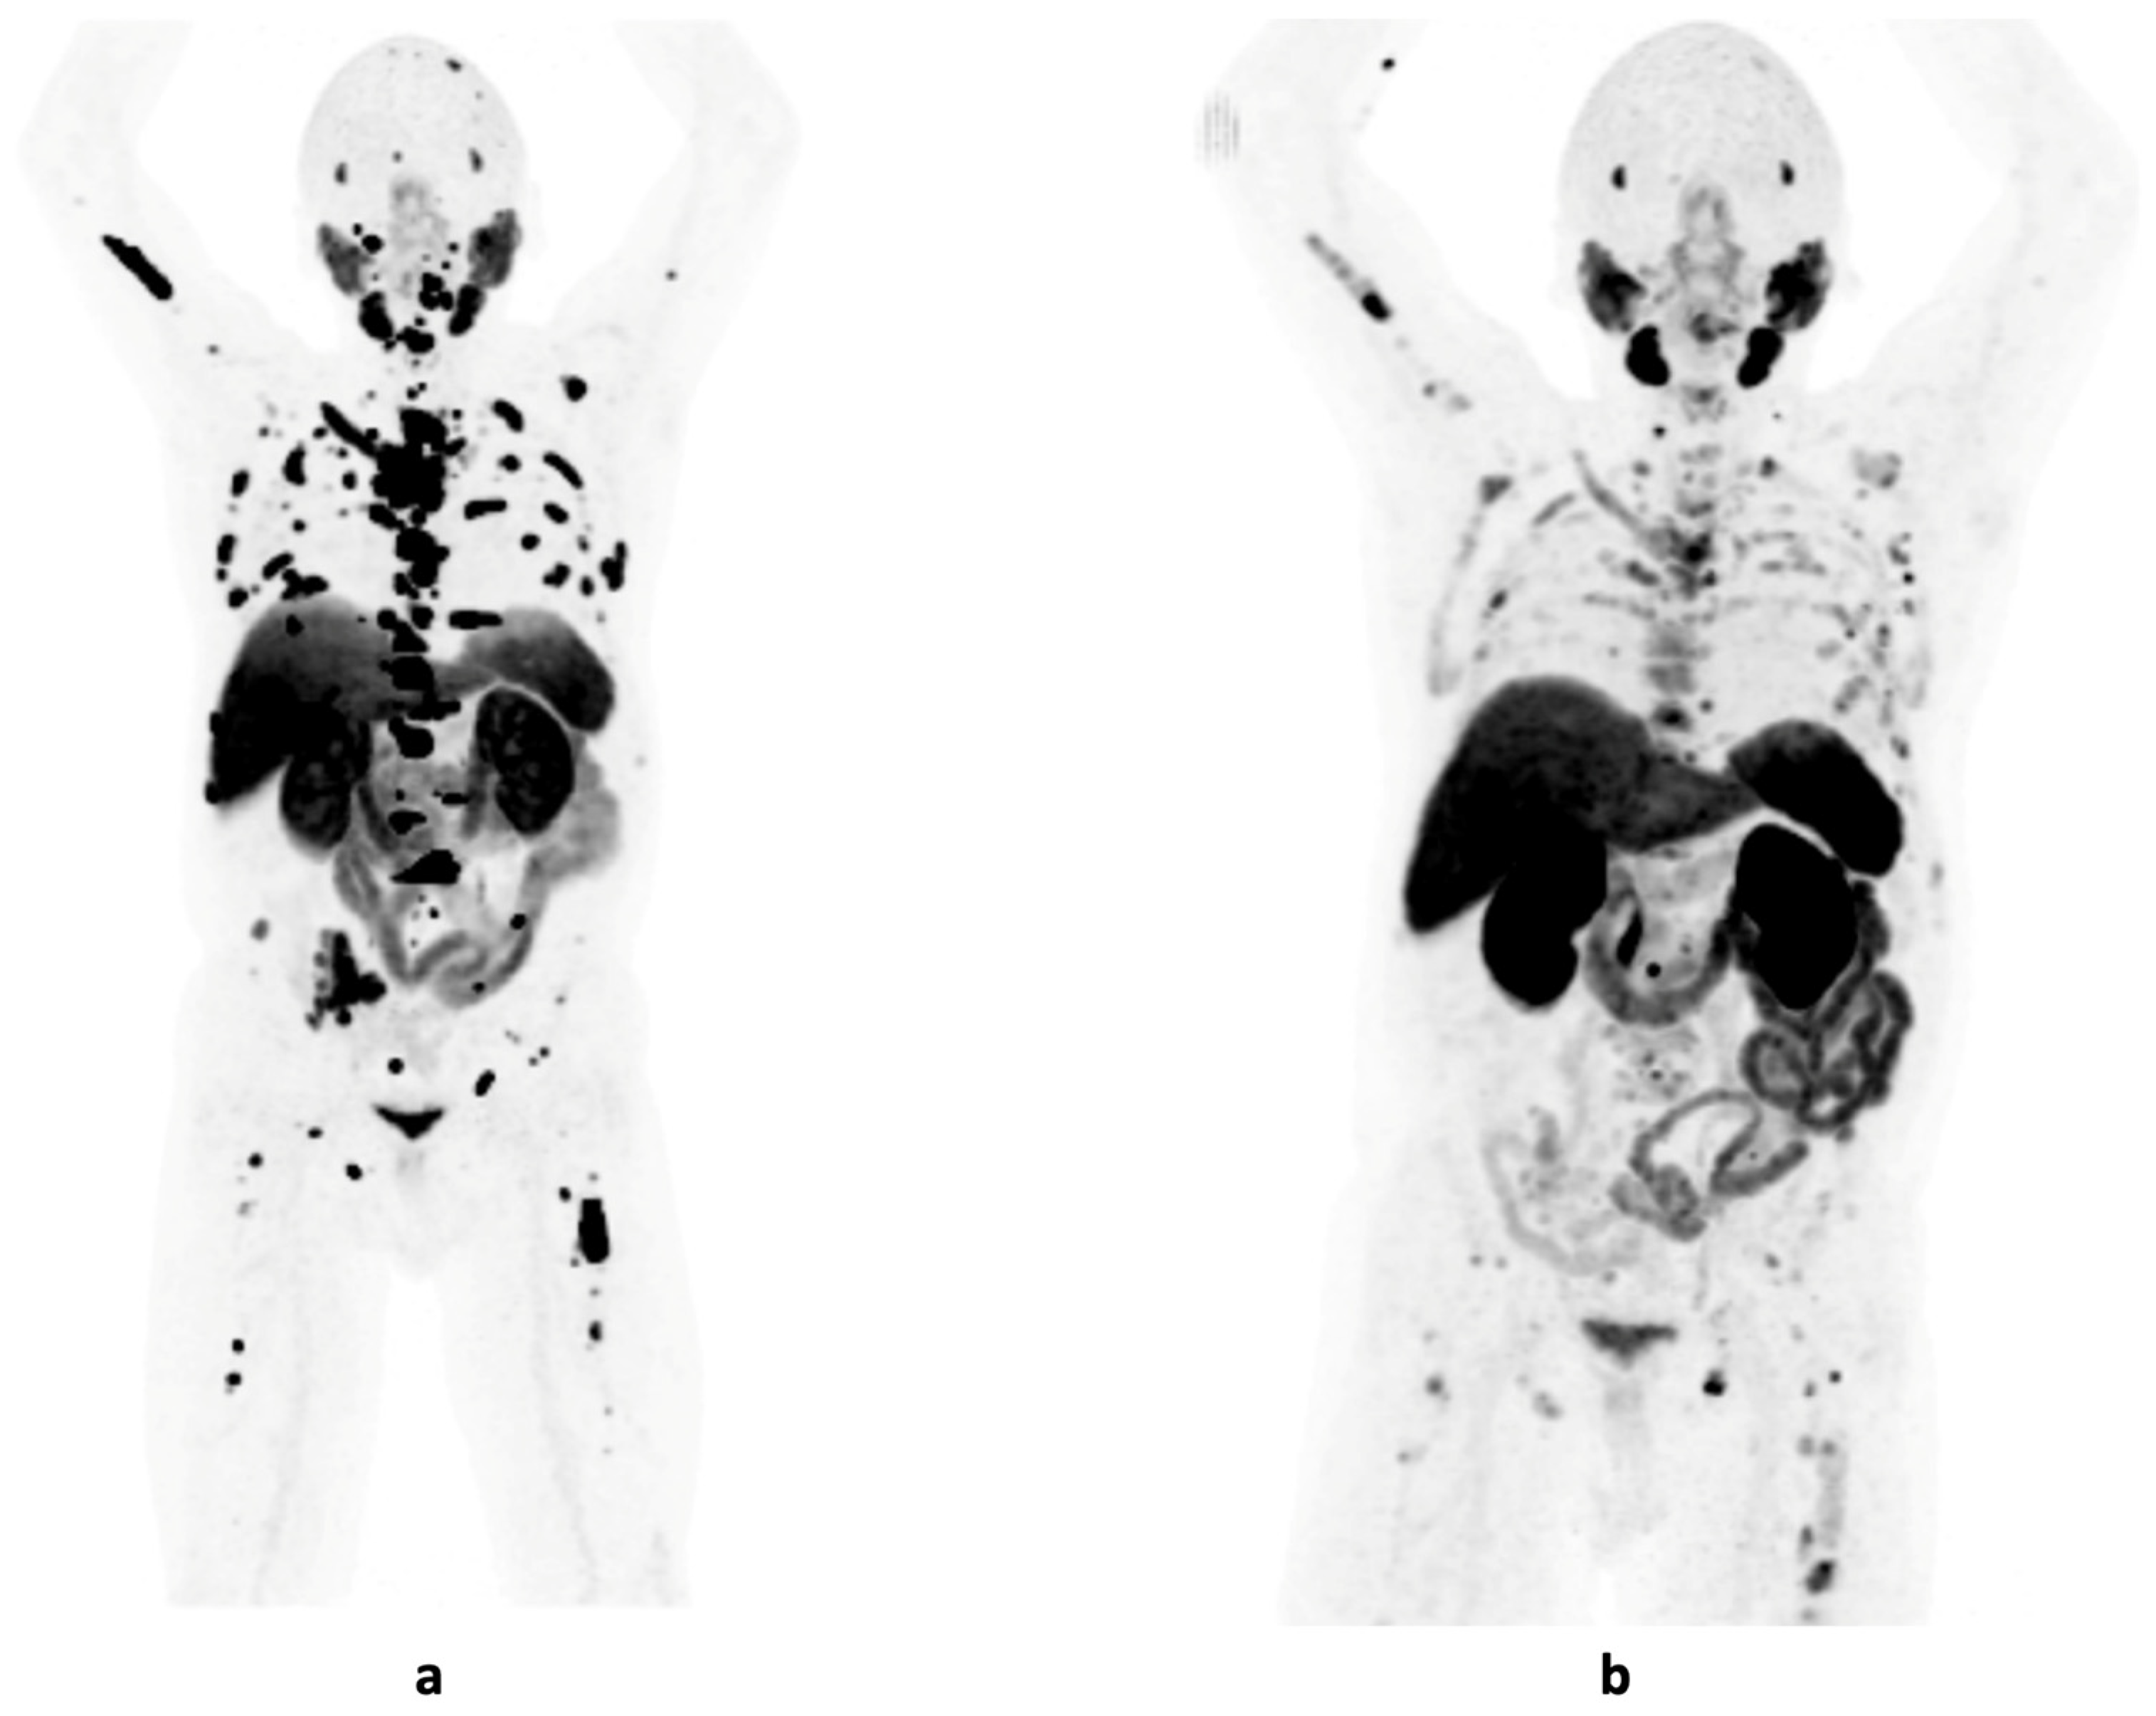

2. Imaging Modalities and PSMA Targeting in PCa

4. PSMA-PET in Primary Staging of PCa

5. PSMA-PET After Treatment with Curative Intent

5.2. Biochemical Recurrence

6. PSMA-PET in Castration-Resistant PCa